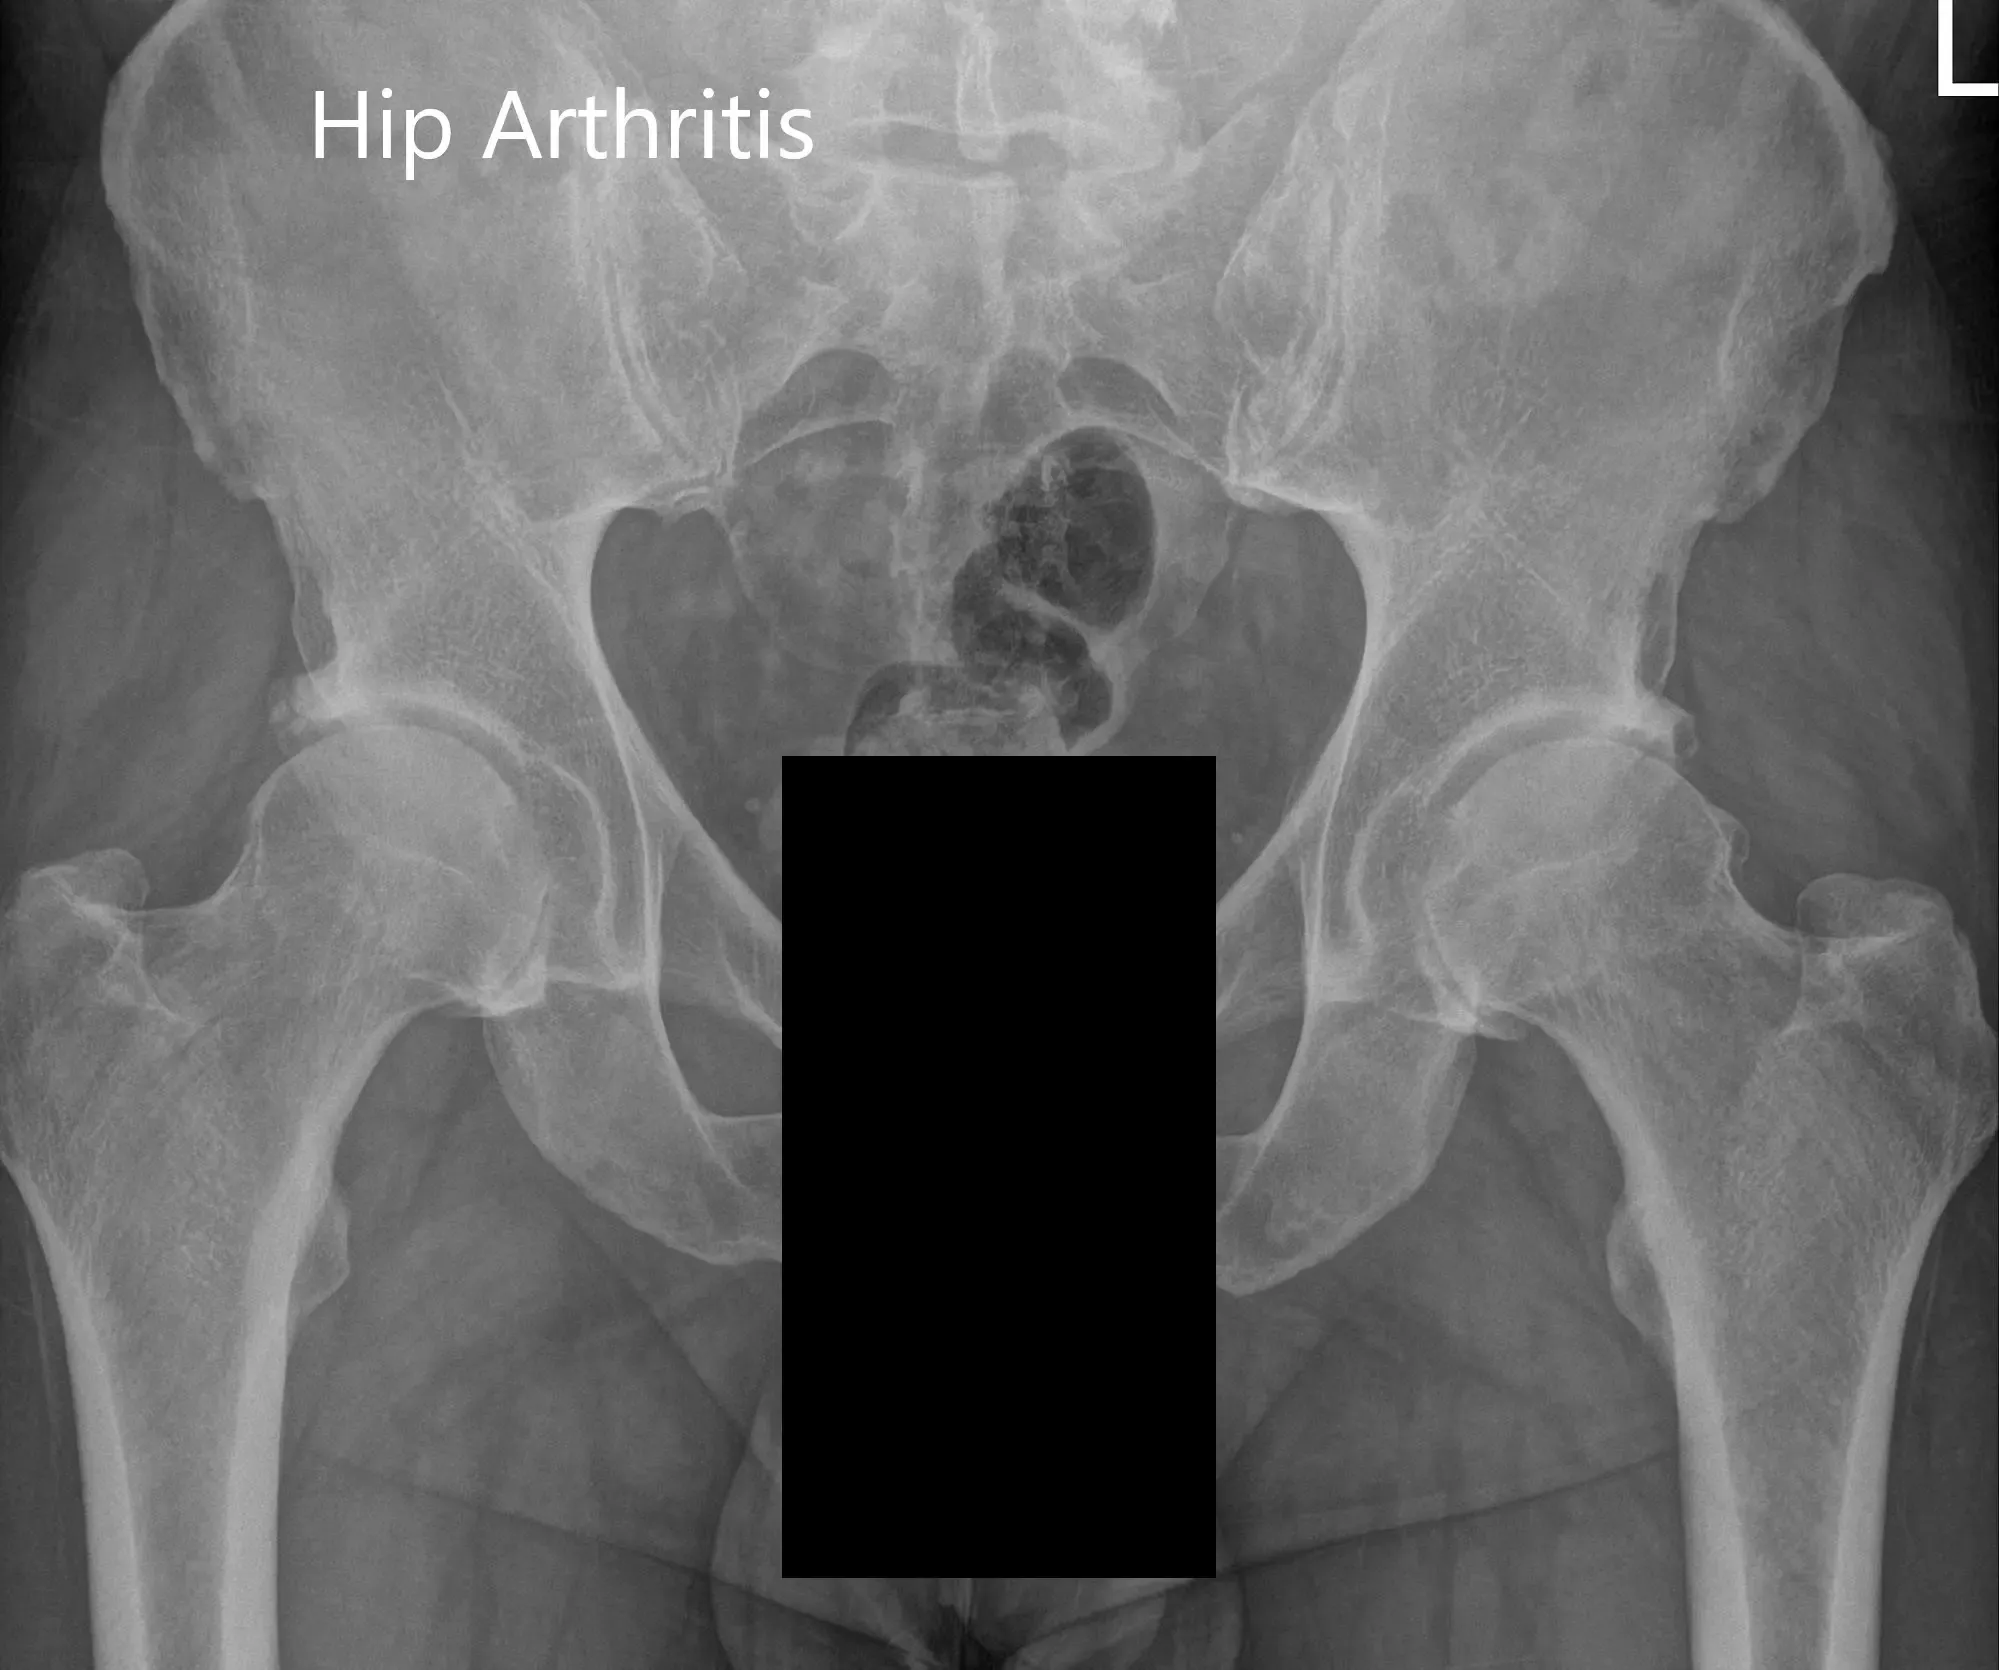

Sus estudios de imagen revelaron cambios de artritis en ambas caderas. Teniendo en cuenta que su dolor de cadera limita el estilo de vida, se le aconsejó someterse a un reemplazo total bilateral de cadera. También se discutieron extensamente con ella y con su marido los riesgos, beneficios y alternativas. Ella aceptó seguir adelante con la prótesis de cadera izquierda.

Radiografía preoperatoria de la vista de la pelvis y la vista lateral de la cadera izquierda.